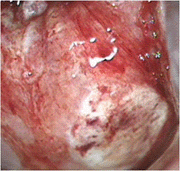

자궁경부암 환자의 자궁경부 이미지

[자궁경부암 환자의 자궁경부]